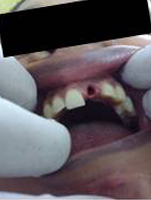

After Placement of Prosthesis

Single Tooth Implant